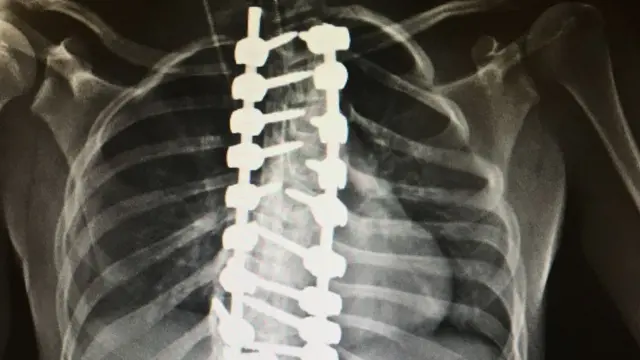

Ameliyatta Megan'ın omuriliğine dört metal çivi yerleştirilmiş.